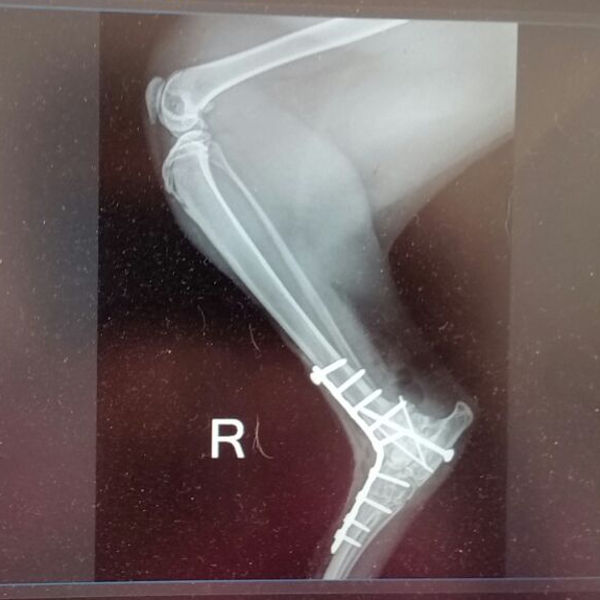

Doch leider stand mir Anfang Oktober ein großer Schock bevor. In einer Facebook-Gruppe tauchte auf einmal ein Bild einer verletzten, getigerten Katze auf. Da sie bei der benachbarten Hundeschule gefunden worden war, dachte ich, dass das es eventuell eine von meinen Stallkatzen sein könnte. Ich bin zu der Tierärztin im Nachbarort gefahren, zu der die Katze gebracht worden war. Der Abgleich der Tätowierungen in den Ohren bestätigte, dass die Katze zu mir gehörte. Als nächstes wurde mir mitgeteilt, dass die Katze zwei Tage lang unentdeckt in einem Maschendrahtzaun gehangen hatte. Der Besitzer der Hundeschule hatte sie schließlich zufällig entdeckt und aus dem Zaun herausgeschnitten. Eines der Hinterbeine stürbe ab und müsse daher amputiert werden, sollte ich mich nicht fürs Einschläfern entscheiden.

Eine Einschläferung habe ich vehement abgelehnt. Frau Wanninger sah das ebenso. Also habe ich den Kater zu einem Chirurgen gefahren, wo er zwei Tage später erfolgreich operiert wurde. Ich hatte an keinem Tag Bedenken, dass Max – so heißt der vierjährige Kater nun – mit seiner Behinderung nicht zurecht kommen würde.